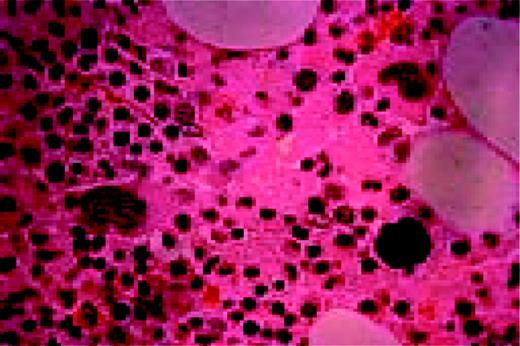

M7. Bone marrow biopsy in a patient with acute nonlymphoblastic leukemia, FAB type M7. Abnormal megakaryoblasts and megakaryocytes as well as fibrosis are seen in this H&E-stained field.FIG84

Slide MG3